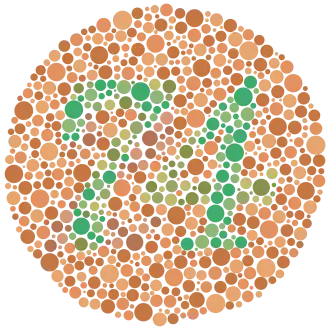

Ejemplo de una carta de color Ishihara. El número "74" debe ser claramente visible para los individuos con visión normal. Las personas con tricromacia pueden leer "21", y aquellos con acromatopsia no distinguen ningún número. | ||

El daltonismo es una afección de origen genético, que afecta a la capacidad de distinguir los colores. La palabra daltonismo proviene del químico y matemático John Dalton, que la estudió.[1][2] El grado de afectación es muy variable, oscila entre la falta de capacidad para discernir cualquier color (acromatopsia) y un ligero grado de dificultad para discriminar matices de rojo y verde. A pesar de que la sociedad en general considera que el daltonismo pasa inadvertido en la vida diaria, supone un problema para los afectados en ámbitos tan diversos como valorar el estado de frescura de determinados alimentos, identificar códigos de colores de planos o elegir determinadas profesiones para las que es preciso superar un reconocimiento médico que implica identificar correctamente los colores (militar de carrera, piloto, capitán de marina mercante, policía, árbitro de fútbol, entre otras). Puede detectarse mediante test visuales específicos como las cartas de Ishihara. [3] Los varones tienen más probabilidades de ser daltónicos que las mujeres, porque los genes responsables de las formas más comunes de daltonismo se encuentran en el cromosoma X, las mujeres no daltónicas pueden portar genes de daltonismo y transmitirlos a sus hijos. Las alteraciones en la visión del color se llaman discromatopsias, dependiendo de su origen pueden ser hereditarias o adquiridas en la vida adulta, la palabra daltonismo designa solamente a las alteraciones de la visión del color congénitas o hereditarias, las formas adquiridas pueden ser consecuencia de otras alteraciones en el ojo, el nervio óptico o partes del cerebro.[4] No existe cura para el daltonismo, algunas lentes especiales o lentes de contacto pueden ayudar a pacientes con daltonismo en algunas tareas, pero no otorgan al usuario una visión normal del color.[5] [4] [6]

El procedimiento más empleado para el diagnóstico, aunque no el único, son las cartas de Ishihara. Consiste en una serie de 38 láminas en las que es preciso identificar un número que se encuentra insertado en la misma.